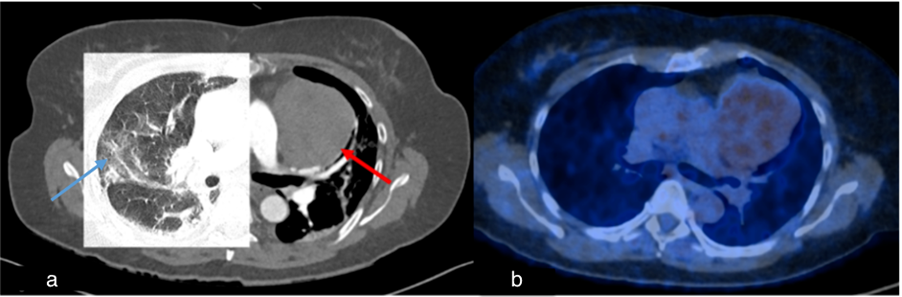

Figure 4.

Case 1, a 67-year-old female. (a) Initial chest CT to clarify pulmonary embolism or post-COVID-19 findings showed concentric wall thickening of the thoracic aorta (red arrow), indicating large vessel vasculitis. No pulmonary infiltrates or post-COVID-19 findings were observed. (b) Follow-up computed tomography 2 months later showed indeterminate appearance of recurrent COVID-19 pneumonia (blue arrow) and regressed arterial wall thickening (red arrow).